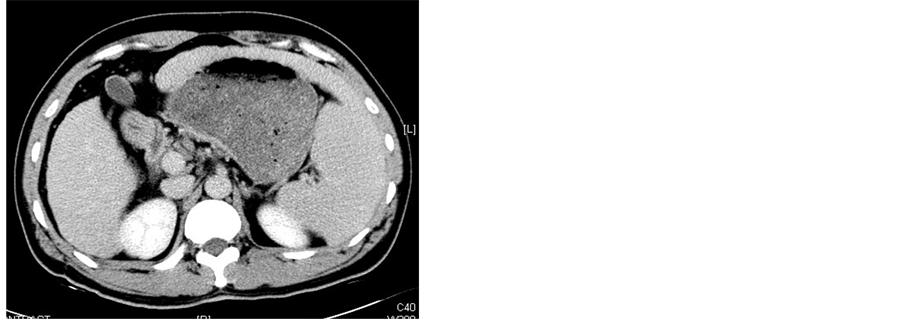

All patients underwent abdominal CT scanning (GE Medical Systems) 1 wk before procedure and 2 wk after procedure to evaluate the necrosis of the spleen (Figure 2). After treatment with MWA combineed with TACE, all patients remained in hospital with their adverse effects or complications observed and were then followed up at outpatient clinic. Peripheral blood cell parameters including white blood cells (WBC), platelets (PLT) and red blood cells (RBC) were obtained 1 wk before procedure and 1 wk, 2 wk, 1 mo, 2 mo, 3 mo after procedure.

Figure 2. (a)-(c) Contrast-enhanced CT scans of the spleen before splenic MWA; (d)-(f) Two weeks after MWA. Contrast-enhanced CT scans showed unenhanced low attenuation ablated area in inferior part of spleen. The ablation ratio was about 20%.